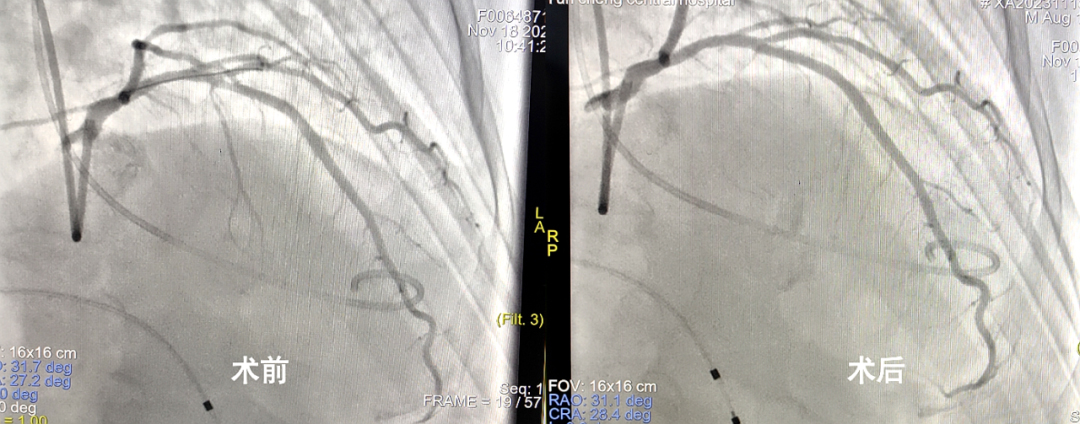

术中,选定目标间隔支后,袁建松教授将OTW球囊准确定位后加压堵塞间隔支,运城市中心医院超声科冯大鹏医生配合观察各项指标,估测符合手术要求。之后,袁建松教授分次缓慢注入无水乙醇注射液,并严密观察患者心律、血压变化,判断消融终点,最终患者左心室测压力下降至122/23mmHg左右,回撤导管测得左心室流出道压差为12mmHg左右,达到预计消融效果。手术全程仅用时30分钟,患者无明显疼痛感。术后,患者仅有轻微胸闷不适,血压和心律无明显变化,复查心脏超声提示室间隔厚度降低为14mm,手术成功。